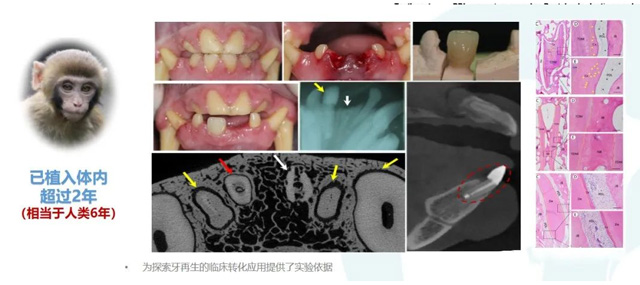

首次在非人灵长类体内验证生物牙根的功能重建